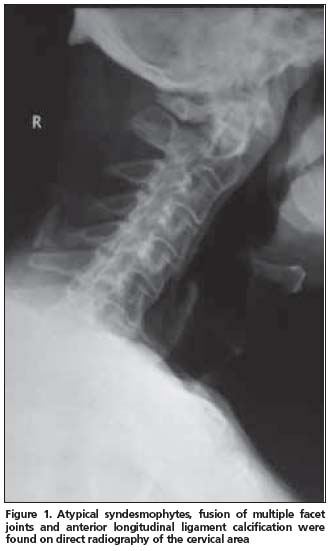

Anterior longitudinal ligament calcification, fusion of multiple facet joints and atypical syndesmophytes were found on cervical spine X-rays (Figure 1) and coarse, asymmetrical syndesmophytes were seen on thoracic (Figure 2) and lumbar spine (Figure 3) X-rays. No abnormalities suggesting PsA or gout were seen on hand and foot radiographs. The magnetic resonance imaging (MRI) of the sacroiliac joint and computerized tomography (CT) of atlanto-axial joint were normal.

PsSpA is observed in 5% of the PsA patients and may be clinically confused with AS[12]. The clinical characteristics of our case also resembled AS. An inflammatory type of low back pain was present and chest expansion was 2 cm. X-rays revealed a predominance of axial involvement. However, a normal sacroiliac joint MRI and lack of a typical syndesmophyte appearance made the AS diagnosis unlikely.

Another striking radiologic finding in our patient was that cervical spine involvement was on the foreground. Queiro et al. reported the cervical spine involvement in HLA-B27- negative PsSpA patients to be 51%[13]. Cervical spine involvement in PsA is known to be seen more commonly in patients presenting with psoriatic lesions on hairy skin[12]. The majority of skin lesions were localized on the hairy skin in our patient. Radiographic abnormalities are not sufficiently sensitive and specific for the diagnosis of gout. Only 45% of patients with gout manifest radiographic bone changes, and then only six to eight years after the initial attack. The radiographic hallmarks of gout are normal mineralization, joint space preservation, sharply marginated erosions with sclerotic borders, overhanging edges, and asymmetric polyarticular distribution[14]. Radiologic evaluation of our patient did not reveal any of these images.